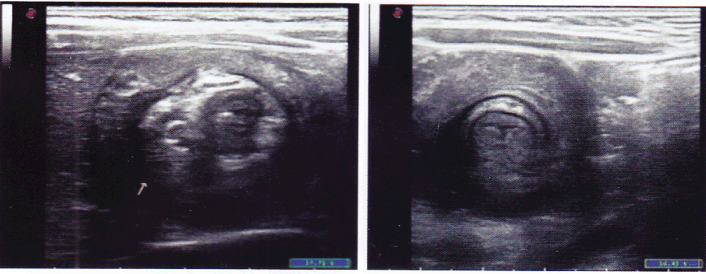

患儿,男性,2岁,突发腹痛,哭闹不止就诊,超声所见如图所示,最可能的诊断是()。

A、急性阑尾炎

B、肠套叠

C、肠道占位性病变

D、肠道蛔虫

E、以上都不对

B